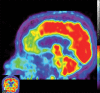

Neurodegenerative diseases are a devastating group of disorders that can be difficult to accurately diagnose. Although these disorders are difficult to manage owing to relatively limited treatment options, an early and correct diagnosis can help with managing symptoms and coping with the later stages of these disease processes. Both anatomic structural imaging and physiologic molecular imaging have evolved to a state in which these neurodegenerative processes can be identified relatively early with high accuracy. To determine the underlying disease, the radiologist should understand the different distributions and pathophysiologic processes involved. High-spatial-resolution MRI allows detection of subtle morphologic changes, as well as potential complications and alternate diagnoses, while molecular imaging allows visualization of altered function or abnormal increased or decreased concentration of disease-specific markers. These methodologies are complementary. Appropriate workup and interpretation of diagnostic studies require an integrated, multimodality, multidisciplinary approach. This article reviews the protocols and findings at MRI and nuclear medicine imaging, including with the use of flurodeoxyglucose, amyloid tracers, and dopaminergic transporter imaging (ioflupane). The pathophysiology of some of the major neurodegenerative processes and their clinical presentations are also reviewed; this information is critical to understand how these imaging modalities work, and it aids in the integration of clinical data to help synthesize a final diagnosis. Radiologists and nuclear medicine physicians aiming to include the evaluation of neurodegenerative diseases in their practice should be aware of and familiar with the multiple imaging modalities available and how using these modalities is essential in the multidisciplinary management of patients with neurodegenerative diseases.©RSNA, 2020.